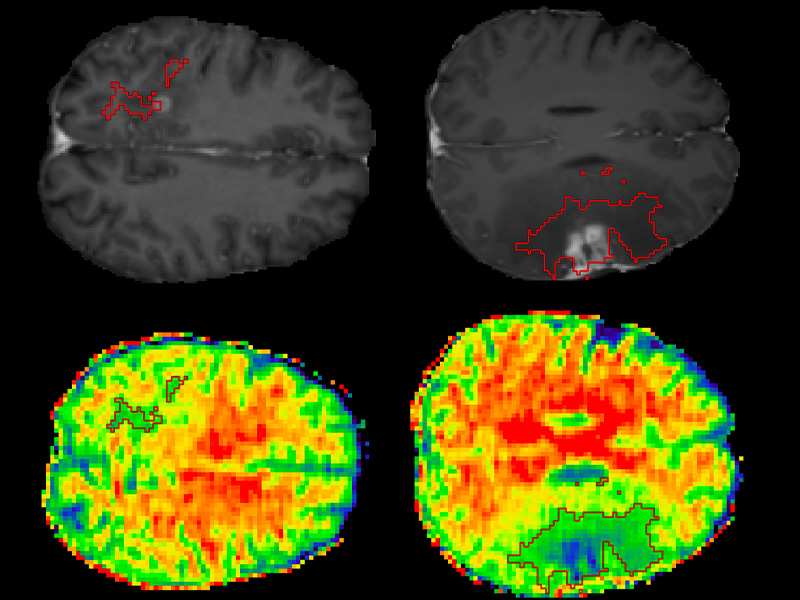

Smart Surveillance of Brain Tumors

Smart Surveillance of Brain Tumours

Clinical surveillance of brain tumours is typically a manual task aimed at assessing tumour growth and transformation. We are working closely with neurosurgeons and radiologists to develop an algorithm that automatically carries out tumour grading from non-contrast enhanced 3D MRIs.